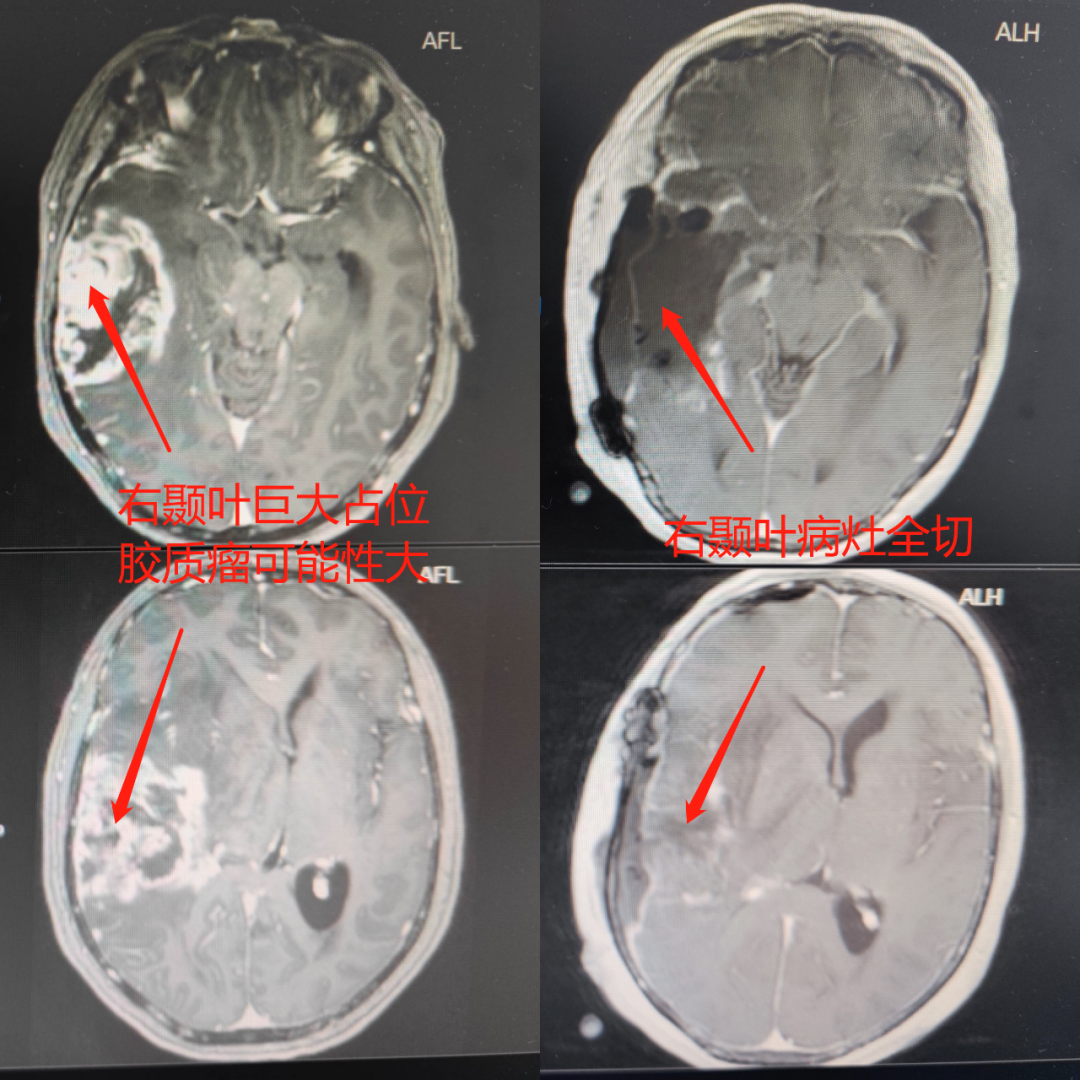

基于患者病情,神经外科主任、主任医师钟斌当即组织技术团队进行病例讨论,制定治疗方案,并耐心、细致地向家属解释疾病的相关知识和手术治疗必要性及过程。最终,家属决定在对其母亲隐瞒真相的情况下施行手术治疗。转科的第二天,卢阿姨脑内的肿瘤摘除手术顺利进行。病检证实卢阿姨脑肿瘤是“胶质母细胞瘤”,是中枢神经系统最常见的、恶性程度最高的星形细胞瘤,属于恶性肿瘤。术后2周,予以同步放化疗和中医药综合治疗,恢复良好。卢阿姨及家人非常满意,开心地出院了。事后卢阿姨得知自己做了“开颅脑瘤切除”手术,虽然心有余悸,但她说她很幸运,选择了好医院好医生,发现得早,治疗及时、效果好!